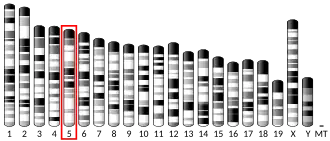

The BRCA2 gene is located on the long (q) arm of chromosome 13 at position 12.3 (13q12.3).[16] The human reference BRCA2 gene contains 27 exons, and the cDNA has 10,254 base pairs[17] coding for a protein of 3418 amino acids.[18][19]